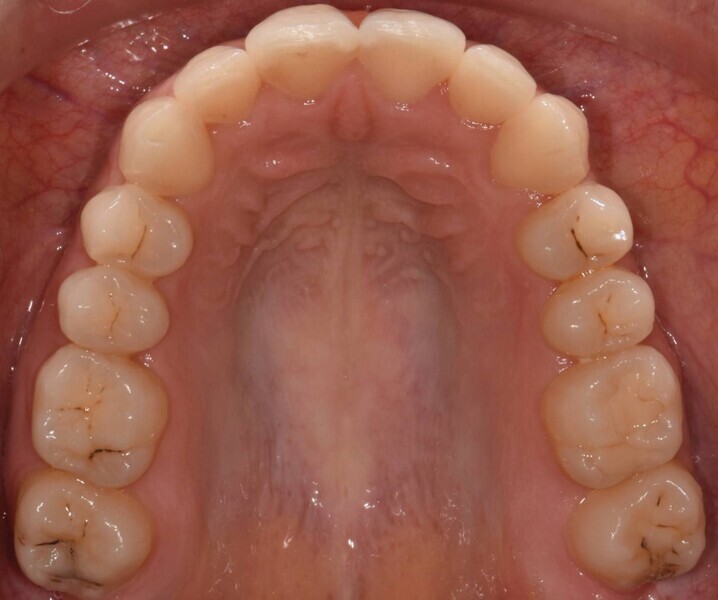

Après une période de onze mois et un nombre total de 66 aligneurs maxillaires et mandibulaires, le traitement est terminé et tous les objectifs sont atteints, à savoir une relation bilatérale de Classe I, une symétrie des arcades et la correction de l’encombrement (Fig. 6).

Fig. 6a : Photographie intraorale finale.

Fig. 6b : Photographie intraorale finale.

Fig. 6c : Photographie intraorale finale.

Fig. 6d : Photographie intraorale finale.

Fig. 6e : Photographie intraorale finale.